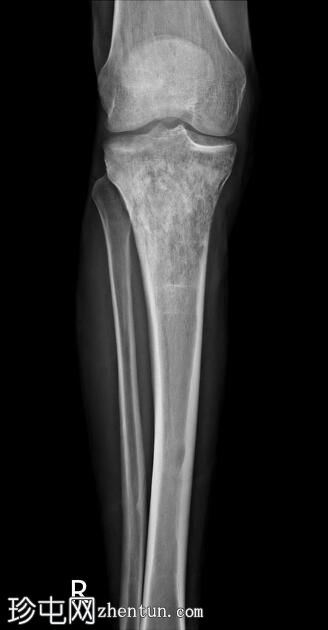

4.jpg

矢状位片

T1加权像

股骨外侧髁前外侧面、胫骨近端及髌骨上极可见异常信号(T1加权像低信号,T2/PD脂肪抑制序列呈不均匀高信号)浸润性病变,伴有边界不清的过渡带。可见少量骨外成分。